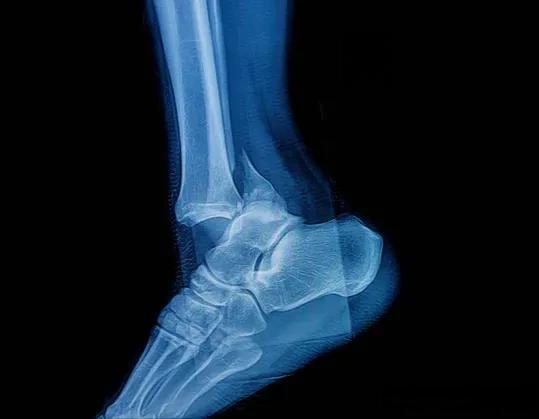

老年人要预防骨折,小弟早上摔了一跤,脚踝粉碎性骨折进医院了

老年人骨折已成为一个日益严重的公共卫生问题。 据统计,髋部骨折后约50%的患者无法恢复独立生活能力,甚至可能缩短寿命。这一严峻现实凸显了预防老年人骨折的紧迫性。